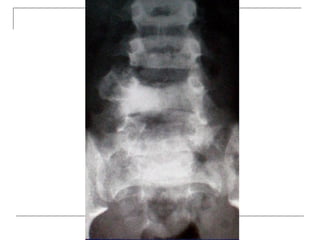

 AP

-loss of lumbar lordosis

-reduced disc space

-osteophytes

-deformity

-fracture (increase interpedicular distance)

-osteoporosis

-pedicle disruption

Plain x-rays